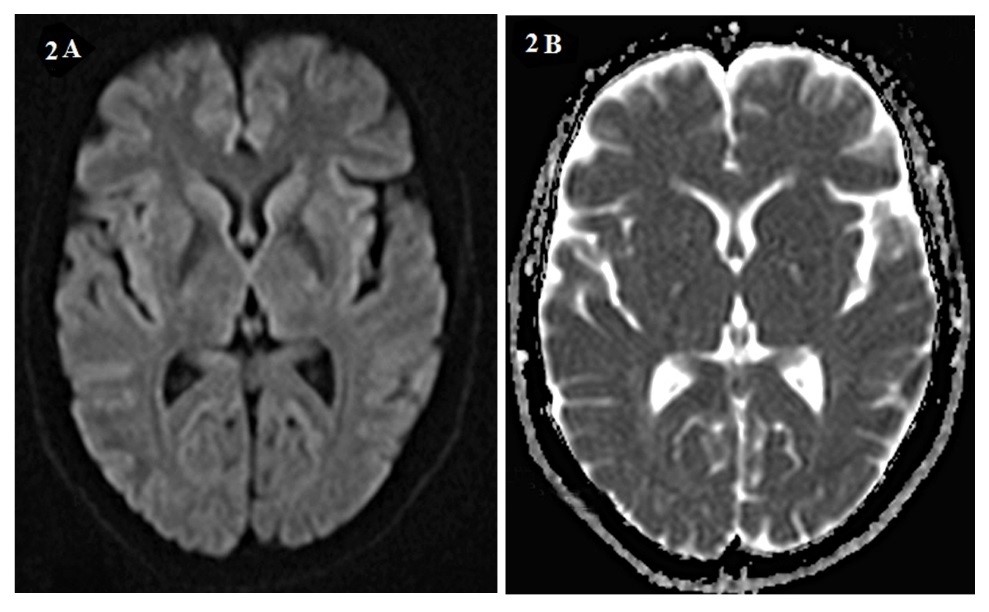

Background: Creutzfeldt-Jakob disease (CJD) is a progressive and fatal prion disease in human and its annual incidence is estimated one per million. Sporadic form of CJD is the most common form of the disease that involved 85% of cases. Case Report: We presented two cases of CJD with the different clinical presentation; a 58-year-old woman who referred with amnesia, depression and a 59-year-old woman with ataxia as her chief complaint. Based on the findings and roled-out the other differential diagnosis, the CJD was confirmed. Both of them died before 12 months after diagnosis. Conclusion: Although CJD is a rare disease with different clinical manifestation, it is considered as one the differential diagnosis of progressive dementia.[GMJ.2019;8:e1357]Â